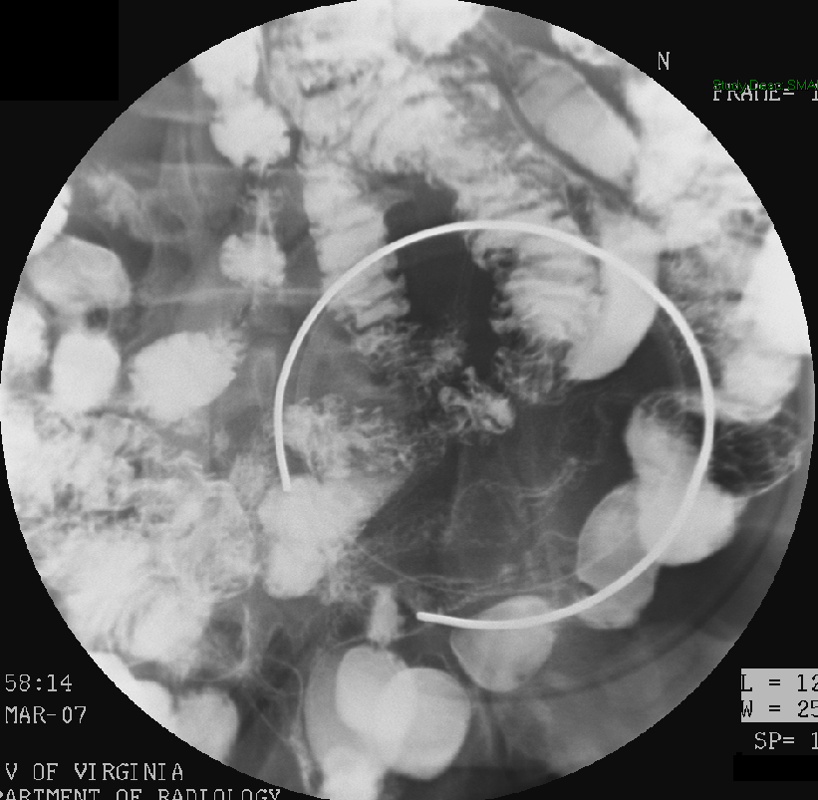

- nasojejunal

(key image 2)